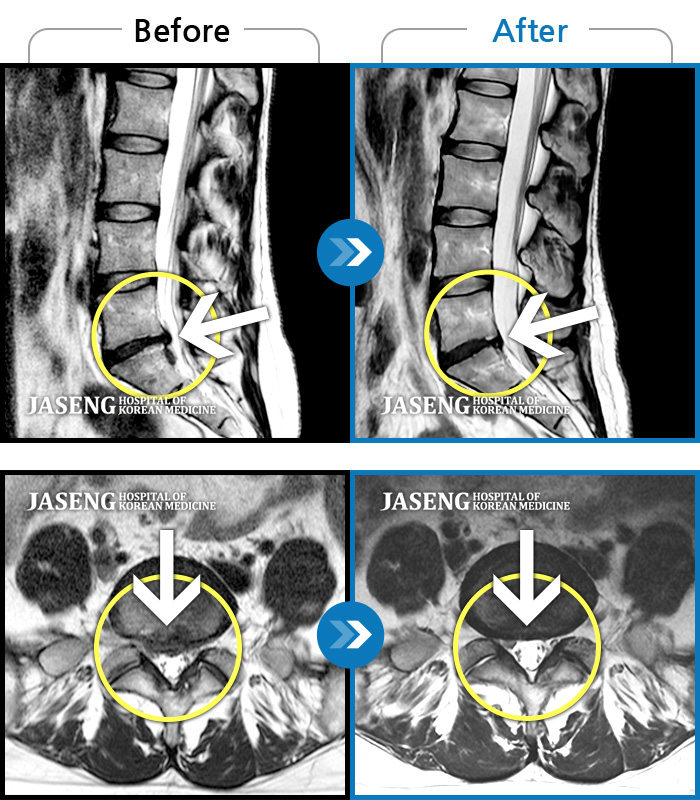

자생 비수술 한방통합치료 후

터진디스크가 흡수된 모습

Before

터진디스크 한방통합치료 전

After

터진디스크 한방통합치료 후

비수술 치료만으로

터진 디스크 흡수

튀어나온 디스크 대비,

터진 디스크 치료 효과 우수

디스크 흘러내린 정도가

심할수록 흡수 가능성 증가

치료 후 장기추적관찰 결과,

환자 90% 이상 치료 만족